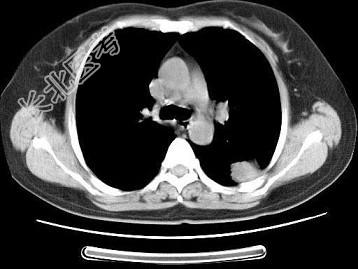

- 单项选择题女,52岁, 左侧背痛1月,胸部CT如图, 最可能的诊断为 ( )

A、左肺中央型肺癌

B、左肺周围型肺癌

C、左肺感染

D、左肺炎性假瘤

E、肺隔离征